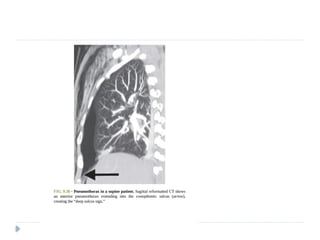

 CT

 Provided lung windows are examined, a

pneumothorax is very easily identified on CT, and

should pose essentially no diagnostic difficulty.

 pneumothorax is imaged as air in the pleural

space outside the lung and visceral pleura.

 Even a very small pneumothorax is visible in the

anterior pleural space.

 Its diagnosis is usually straightforward, although

differentiating a medial pneumothorax from

pneumomediastinun may be difficult in some

cases.

 CT  Providedlung windows are examined, a pneumothorax is very easily identified on CT, and should pose essentially no diagnostic difficulty.  pneumothorax is imaged as air in the pleural space outside the lung and visceral pleura.  Even a very small pneumothorax is visible in the anterior pleural space.  Its diagnosis is usually straightforward, although differentiating a medial pneumothorax from pneumomediastinun may be difficult in some cases.